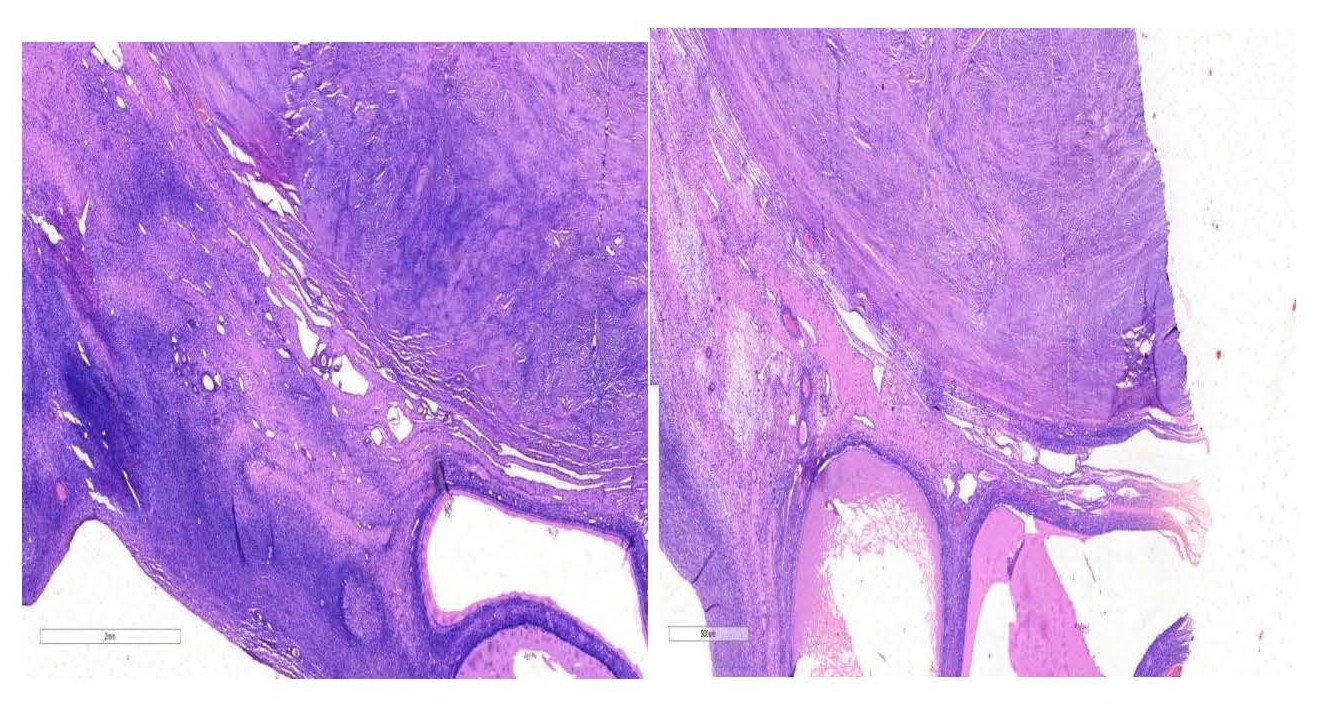

Figure 2. Micrograph demonstrating leiomyoma adjacent to ovarian tissue containing cystic follicles (×20 magnification).

Figure 3. Micrographs showing leiomyoma with adjoining ovarian tissue which shows cystic follicles X40 magnification.